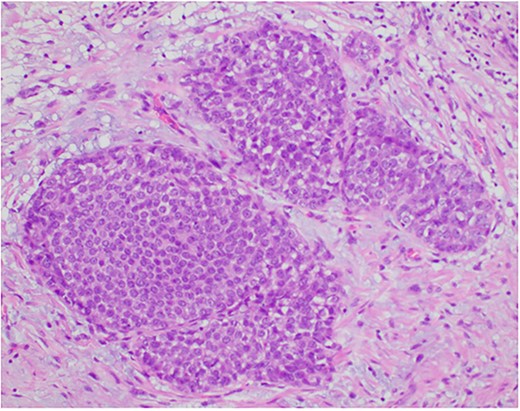

A 26-year-old female presented with a longstanding palpable fibroadenoma in the left breast. She was first investigated with ultrasound imaging showing a lobulated 2.4 × 2.5 × 1.4 cm hypoechoic lesion with well-defined margins (Fig. 1). She underwent core needle biopsy of the lesion which was histologically proven to be a fibroadenoma. There was no evidence of malignancy. She was later discharged and presented 6 years later with a history of recent enlargement of the left breast lump. Ultrasound imaging now showed increase in the size of the left breast fibroadenoma to 3.2 × 2.7 × 1.6 cm and development of an irregular outline (Fig. 2). Because of increasing size of the lesion and new indeterminate features, excision biopsy was advised. Post-excision histology revealed a 5-mm focus of classic lobular carcinoma in situ (LCIS) with a 0.6-mm area of microinvasive carcinoma within the fibroadenoma (Figs 3–6). The carcinoma was estrogen and progesterone receptor positive and Her2 negative. Atypical ductal hyperplasia was seen in the breast tissue adjoining the fibroadenoma. After presentation at our multidisciplinary tumor board, sentinel lymph node biopsy for staging of the invasive carcinoma, radiotherapy and endocrine therapy for risk and recurrence reduction, as well as genetic testing in view of her young age was discussed with the patient. Because of the small size of the invasive carcinoma, potential cost and morbidity associated with sentinel lymph node biopsy, no further surgery was performed. The patient was agreeable to proceed with radiotherapy and endocrine therapy but requested to defer genetic testing.

Photomicrograph showing the expanded ducts by classic lobular carcinoma in situ. (HE, ×200).